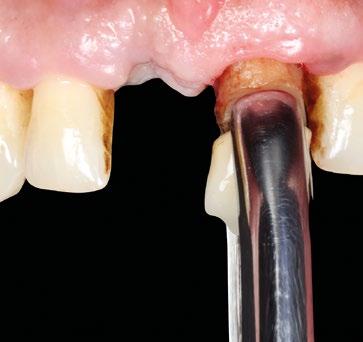

A continuación, se rellena el gap vestibular y el defecto óseo con hueso autólogo y xenoinjerto, con gran atención de que no queden partículas en la zona del injerto conectivo (Fig. 13). Obtención y desepitelización del injerto de tejido conectivo subepitelial del paladar (Fig. 14, 15), y sutura del mismo a la base de las papilas quirúrgicas 1 mm submarginal (Fig. 16).

En este caso decidimos utilizar la corona natural como provisional. Se rebasa en su posición original sobre el cilindro de titanio con composite fluido y se modela el perfil crítico y subcrítico ideal. Es imprescindible acabar y pulir minuciosamente, en especial la parte subgingival, para reducir el acumulo de placa (Fig. 17, 18).

Se finaliza la sutura del CAF con la corona en posición, el trayecto supracrestal de la misma dará apoyo al injerto y al colgajo, que colgajo debe cubrir 1 mm el injerto, y quedar 1 mm más coronal del margen definitivo deseado. En la imagen oclusal se ve la correcta salida del tornillo protésico y el volumen vestibular (Fig 19).